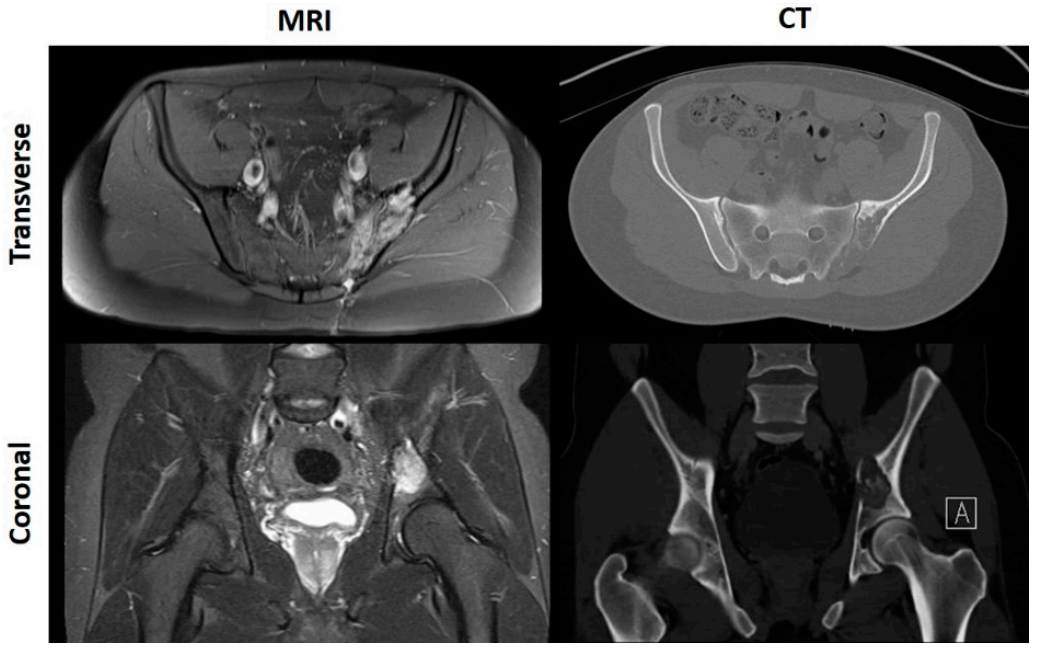

CT scans are excellent at delineating bony anatomy, thereby picking up pathological fractures and assessing ossification and calcification more accurately [17,18]. Nevertheless, as the aforementioned guidelines allude to, MRI is the most accurate tool for the determination of tumour limits within and outside of the bone, as it best defines medullary extent and soft tissue components [19,20,21,22,23]; demonstrated by Figure 1.

Figure 1. MRI and CT scans of a patient with left sided pelvic OS.